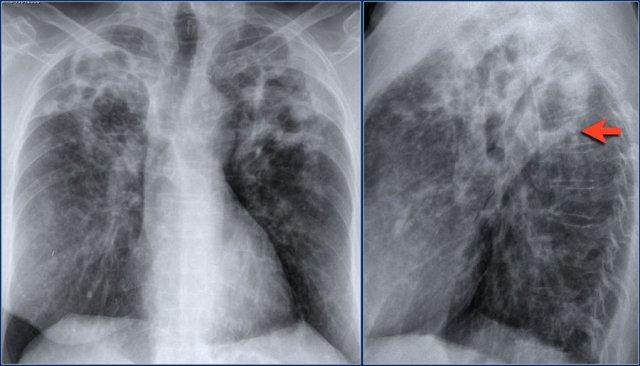

Xẹp thùy trên phổi phải

Hãy quan sát kỹ các hình ảnh trước, sau đó tiếp tục đọc.

Các dấu hiệu:

- Đám mờ hình tam giác

- Rốn phổi phải nâng cao

- Xóa mờ khoang sáng sau xương ức (mũi tên)

Trên PET-CT ghi nhận một khối u phổi kèm theo xẹp thùy trên phổi phải do tắc nghẽn phế quản thùy trên.

Một dấu hiệu thường gặp trong xẹp thùy trên phổi phải là hiện tượng ‘lều hóa’ cơ hoành (mũi tên xanh dương).

Bệnh nhân này có ung thư phổi vị trí trung tâm kèm di căn ở cả hai phổi (mũi tên đỏ).